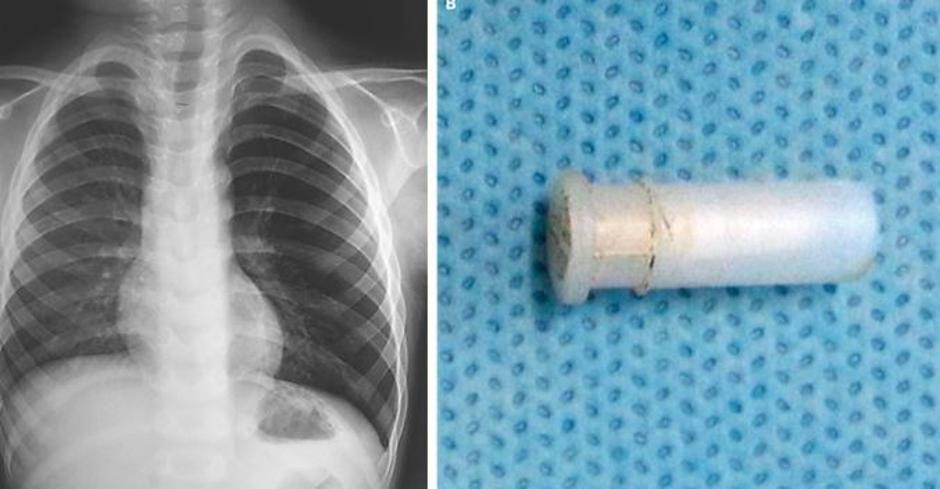

Fatiča so odpeljali na rentgen prsnega koša, kjer jih je čakalo presenečenje, pljuča so bila namreč napihnjena kot balon - preveč ujetega zraka v pljučih imenujemo hiperinflacija.

Zaskrbljeni zdravniki so takoj opravili bronhoskopijo in ugotovili, da se v dečkovih pljučih nahaja igrača - piščalka. "Tuja telesa v dihalnih poteh so pogost pojav, živžgajoči kašelj ob tem pa je izjemno redek,"  je za Live Science dejal Dr. Pirabu Sakthivela z Indijskega inštituta za medicinske vede.

Igračo, ki jo je štiriletnik pogoltnil dva dni prej, so mu odstranili in fant je danes zdrav.